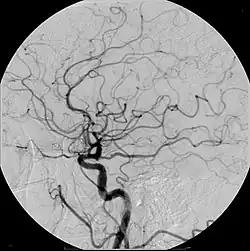

Example of iodine-based contrast in cerebral angiography

Digital subtraction angiography (DSA) is a fluoroscopy technique used in interventional radiology to clearly visualize blood vessels in a bony or dense soft tissue environment. Images are produced using contrast medium by subtracting a "pre-contrast image" or mask from subsequent images, once the contrast medium has been introduced into a structure. Hence the term "digital subtraction angiography.[1][2] Subtraction angiography was first described in 1935 and in English sources in 1962 as a manual technique. Digital technology made DSA practical starting in the 1970s.[3][4]

In order to remove the distracting structures to see the vessels better, first a mask image is acquired. The mask image is simply an image of the same area before the contrast is administered. The radiological equipment used to capture this is usually an X-ray image intensifier, which then keeps producing images of the same area at a set rate (1 to 7.5 frames per second). Each subsequent image gets the original "mask" image subtracted out. (Mathematically, the incoming image is divided by the mask image) The radiologist controls how much contrast media is injected and for how long. Smaller structures require less contrast to fill the vessel than others. Images produced appear with a very pale grey background, which produces a high contrast to the blood vessels, which appear a very dark grey.[5]

DSA is primarily used to image blood vessels. It is useful in the diagnosis and treatment of arterial and venous occlusions, including carotid artery stenosis, pulmonary embolisms, and acute limb ischaemia; arterial stenosis, which is particularly useful for potential kidney donors in detecting renal artery stenosis (DSA is the gold standard investigation for renal artery stenosis[10]); cerebral aneurysms and arteriovenous malformations (AVM).